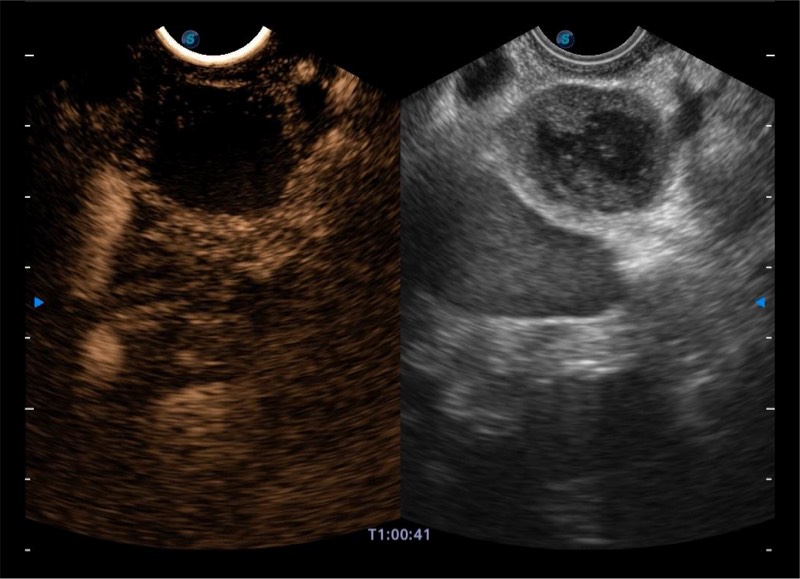

搭载百万级CMOS成像技术

及自主研发凸阵换能器,

可呈现优质的内镜和超声画面

基于二十年的超声技术积累,百老汇电子游戏官网提供了最新一代的独立超声主机,在提供高质量图像的同时满足多学科使用。具备常见多普勒技术并提供弹性成像、声学造影等高端影像技术。新一代传感器具有更强的抗干扰能力并减少图像伪影。